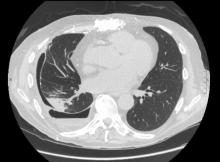

The authors present a case of a 74-year-old man who underwent a bilateral lung transplant. His transplant was done through a clamshell incision. His history was significant for a symptomatic and chronic right recurrent pleural fluid collection that had not responded to nonsurgical management. The operation was performed with the Intuitive da Vinci Xi robotic system. The authors show the use of monopolar scissors, as well as the robotic suction device. The patient recovered very quickly and the authors feel that patients will have significant benefits when surgeons use similar strategies.